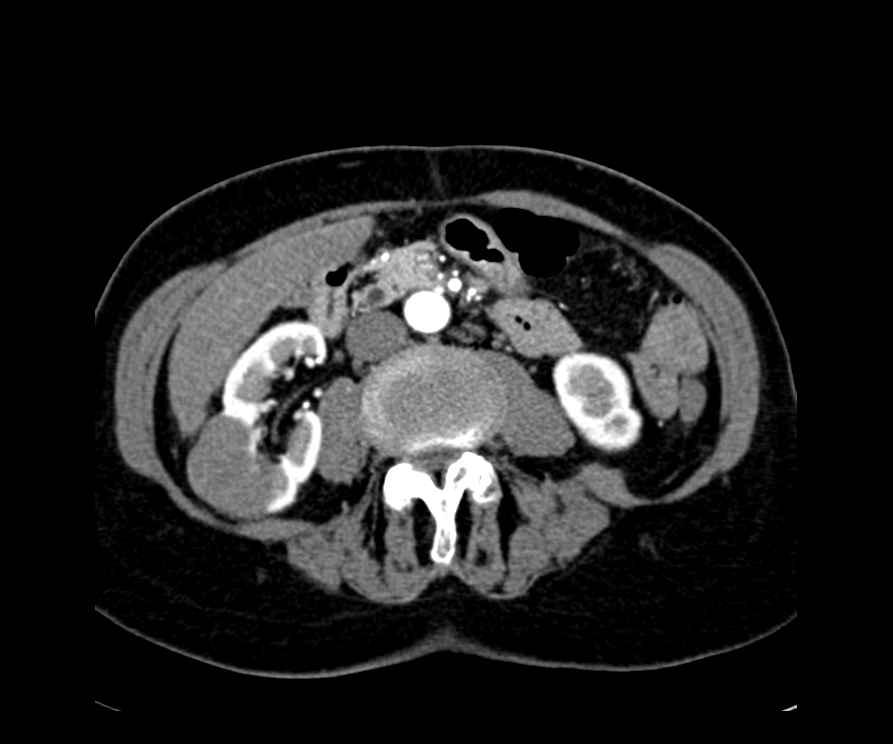

Mediante algoritmos de aprendizaje profundo, transformamos estudios convencionales en mapas anatómicos inteligentes, permitiendo a cirujanos y veterinarios interactuar con la patología de forma dinámica. Este enfoque no solo revela estructuras ocultas, sino que redefine la precisión en la planificación de casos de alta complejidad.

La integración de algoritmos de aprendizaje profundo permite identificar biomarcadores y anomalías tisulares que suelen ser imperceptibles en la radiología convencional. Al analizar la densidad y la textura del dato médico a nivel de píxel, nuestra tecnología facilita la detección precoz de patologías críticas y tumoraciones en estadios iniciales.

Nuestros algoritmos analizan el dato médico (TAC/RM) a nivel de píxel, identificando variaciones de densidad y texturas (radiómica) que pueden ser imperceptibles para el ojo humano. Esto permite detectar anomalías en estadios muy tempranos.

Sí. Al contar con una segmentación inteligente y una delimitación exacta de la masa o lesión antes de la cirugía, el equipo médico puede planificar el abordaje con total exactitud, evitando imprevistos y optimizando cada minuto de la intervención.